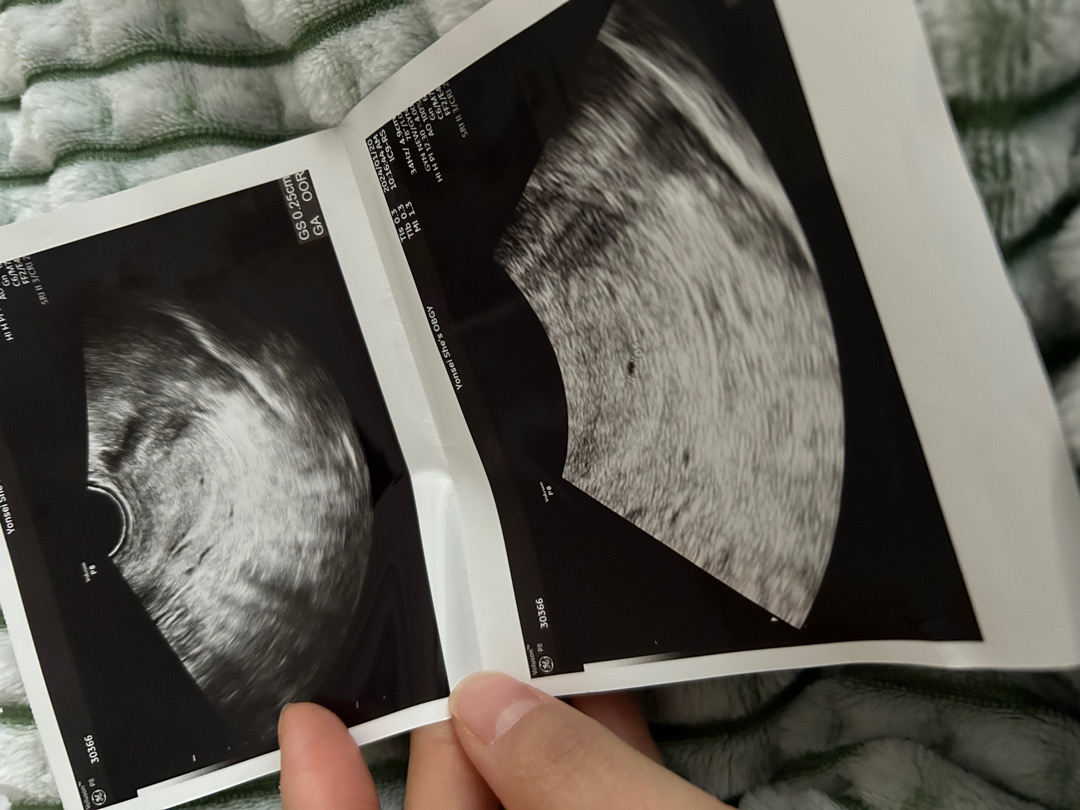

어플 주수로 4주 0일차인데 오늘 촘파로 아기 확인하고 왔어요!! 의사쌤께서 왜이렇게 일찍 왔냐고 ㅋㅋㅋㅋㅋ 너무 빨리와서 안보일수도 있다고 하셨는데 쪼그만 게 존재감 뽐내고 있네요 ㅋㅋ🤣🤣 배란이 빠른 편이라 보인거같다고 하셨어요ㅎㅎㅎㅎ0.25cm..... 2월 초에 심소 들으러 갑니다🥰 근데 3주 들어서자마자 계속 설사하고 먹으면 체하고.. 오늘부터는 뭘 막 먹고싶은 기분도 들고 그르네요🤣